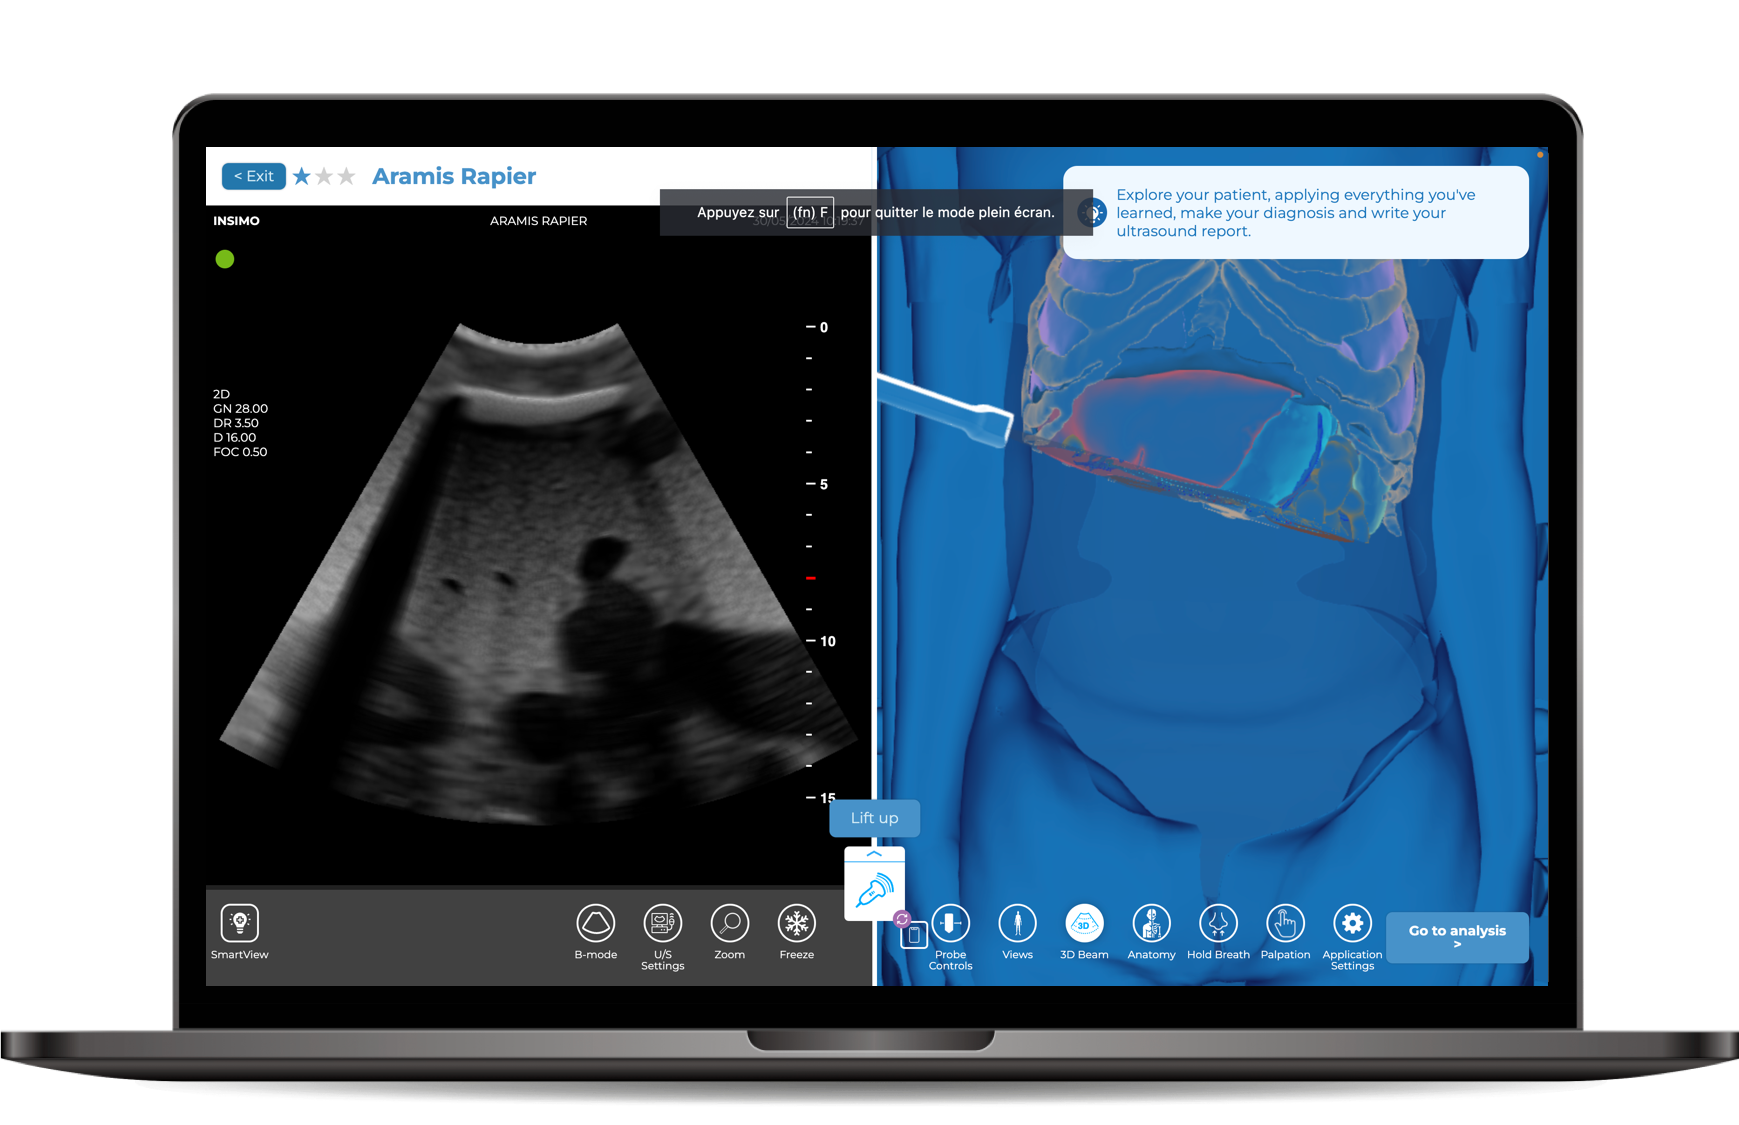

diSplay U/S, simulateur d’échographie en ligne

Module FAST

- Protocole FAST disponible sur notre simulateur d’échographie en ligne diSplay U/S

- Module développé en partenariat avec l’IHU

- 6 exercices guidés pour apprendre les fondamentaux de l’échographie FAST

- 7 cas cliniques : chutes de cheval, impacts frontaux, accidents de moto